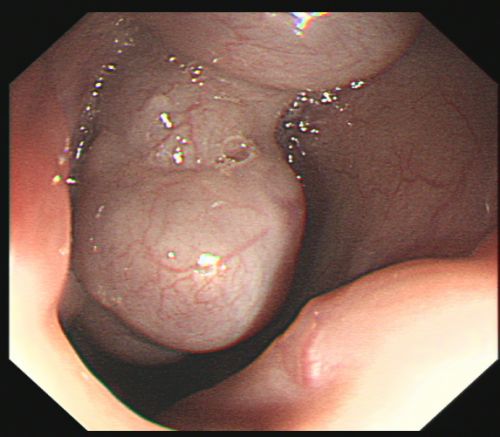

患者入院前后多次解出大量暗红色血便。

胃镜下可以看到食管静脉重度曲张。

经过积极抢救,易某病情稍稳定,被转入综合内科病房继续治疗。入院进一步完善胃镜检查结果提示:食管静脉重度曲张,加上血管壁极薄,随时可能破裂大出血。